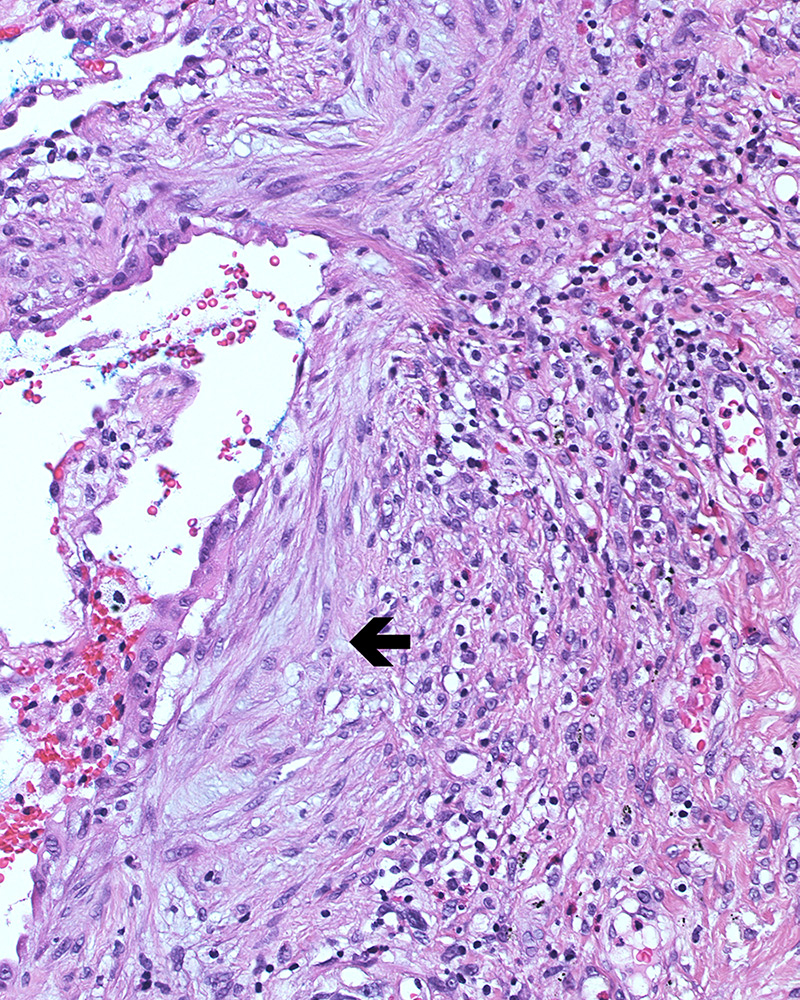

Figure 2

Histological usual interstitial pneumonia pattern: A typical fibroblast focus is shown (arrow). (Haematoxylin and eosin staining; magnification 200x.)

Although the exact pathophysiological mechanism for IPF is still not known in detail, intensive experimental and clinical research efforts shed light on cellular and molecular mechanisms that seem to be essential for the development of the disease. Previous views of inflammation as a central force for fibrosis have been replaced by a concept of impaired alveolar wound healing (fig. 3a‒d) [7, 8]. Histological studies not showing extensive signs of inflammation in UIP and the failure of immunosuppressive therapies in IPF supports rejection of the hypothesis of inflammation-driven fibrosis in this disease [9]. Initial alveolar epithelial type II cell damage by microinjuries and interruption of the basal lamina in the alveoli is considered to be one of the key trigger mechanisms (fig. 3b) [10]. Consecutively released profibrotic factors lead to recruitment, proliferation and differentiation of fibroblasts into myofibroblasts [11, 12], with the formation of typical fibroblast foci (fig. 2) [1]. Production of extracellular matrix by myofibroblasts changes the alveolar architecture with thickening of the air-blood barrier and consecutive impairment of blood gas exchange and lung compliance. This results in hypoxaemia on exertion and at later stages also at rest. Multiple profibrotic pathways have been linked to pulmonary fibrosis progression and are now target of new therapeutic approaches reviewed recently [13]. Transforming growth factor-beta (TGF-β) has been acknowledged as one of the main profibrotic cytokines in IPF [14]. The inactive latent form of TGF-β is activated in IPF via integrins, specifically ανβ6. Active TGF-β mediates profibrotic effects, such as epithelial cell apoptosis, epithelial-mesenchymal transition, extracellular matrix production and differentiation of fibroblasts into myofibroblasts [14]. It also regulates inflammation and can suppress tumour growth. Inhibition of TGF-β thus might lead to undesirable side effects and has to be carefully controlled [14]. Currently, specific antibodies against ανβ6 are being tested in IPF patients to prevent activation from latent to active TGF-β, and other anti-TGF-β targets are in development [15].